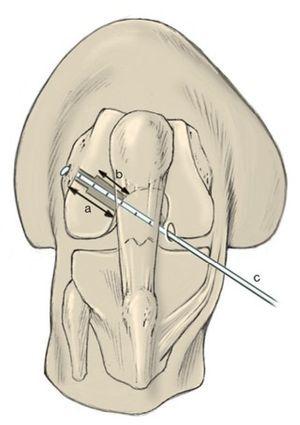

Fig. 9 a) La guía para la colocación del alambre guía para la broca se introduce en la articulación a través del portal medial. En la técnica de perforación de portal se deben utilizar guías diseñadas especialmente para esta técnica (por ejemplo, MPA, Karl Storz, Tuttlingen). Para colocar el alambre guía la rodilla tiene que estar flexionada en más de 110º. b) El gancho doblado de la guía se apoya por detrás de la línea intercondílea en la fascia poplítea. Se pueden elegir varias distancias entre gancho y guía.

Fig. 10 a) El gancho de la guía se desplaza por detrás de la línea inter-condílea. b) A continuación se perfora el alambre guía (2,4 mm) en el centro de la inserción del ligamento cruzado anterior.

Fig. 3 El portal de perforación medial se encuentra justo por encima del cuerno anterior del menisco interno. Se perfora siempre con la técnica de aguja hipodérmica. Conviene que el abordaje no se encuentre demasiado hacia medial para que la broca no lesione el cartílago del cóndilo femoral medial. Si, por el contrario, el túnel se encuentra demasiado lateral, la broca puede salir del túnel por la parte posterior.